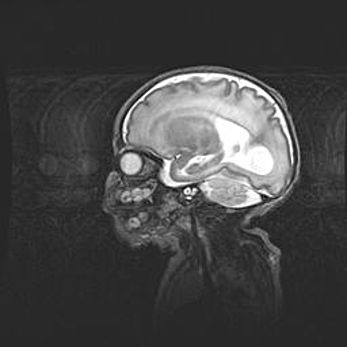

Сообщающаяся гидроцефалия. Кистозная энцефаломаляция головного мозга.

Возраст: 3 месяца 4 дня

Вес: 3100 г

Пол: женский

Окружность головы: 34 см

Срок гестации: 31 неделя

Кистозная энцефаломаляция головного мозга - одна из форм поражения головного мозга в детском возрасте. Характеризуется возникновением множественных и распространённых кист в коре, белом веществе и подкорковых образованиях головного мозга у плодов, новорождённых и детей раннего возраста. Развитие кистозной энцефаломаляции связано с внутриутробной асфиксией и гипотонией, родовой травмой, тромбозом синусов, пороками развития сосудов, инфекциями, сепсисом и другими причинами. Наиболее значимые инфекционные агенты: вирусы простого герпеса, цитомегалии, краснухи, токсоплазмы, энтеробактерии, золотистый стафилококк и другие.